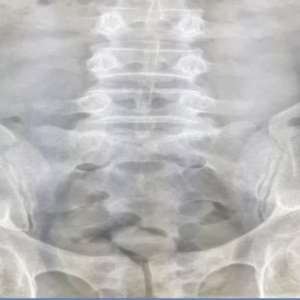

Chiar dacă, la controlul bagajelor nu au fost identificate droguri ascunse, pasagerul a fost examinat și cu aparatul X Ray din dotarea Poliției de Frontieră, fiind observate, în stomacul bărbatului, 18 caşete cu substanţă.